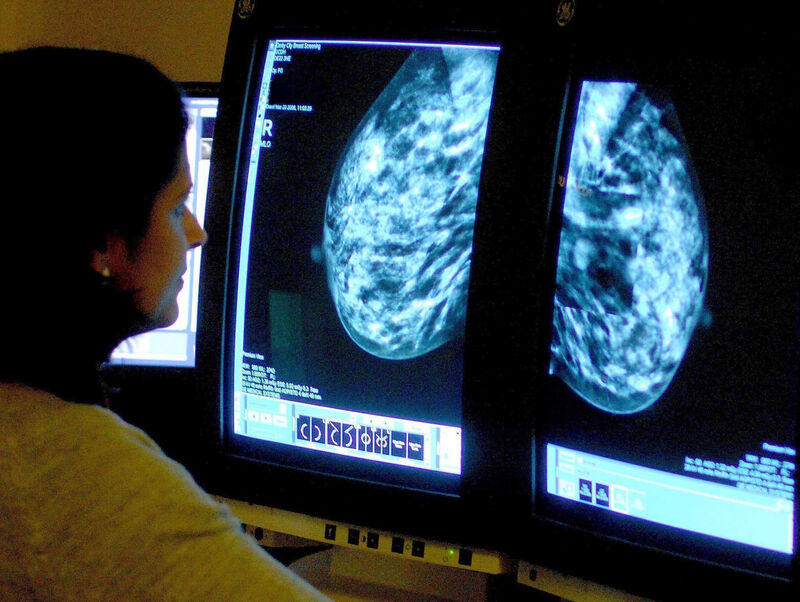

‘I’m grateful to be alive after breast cancer... but a price has been paid’

This month marks Breast Cancer Awareness Month.